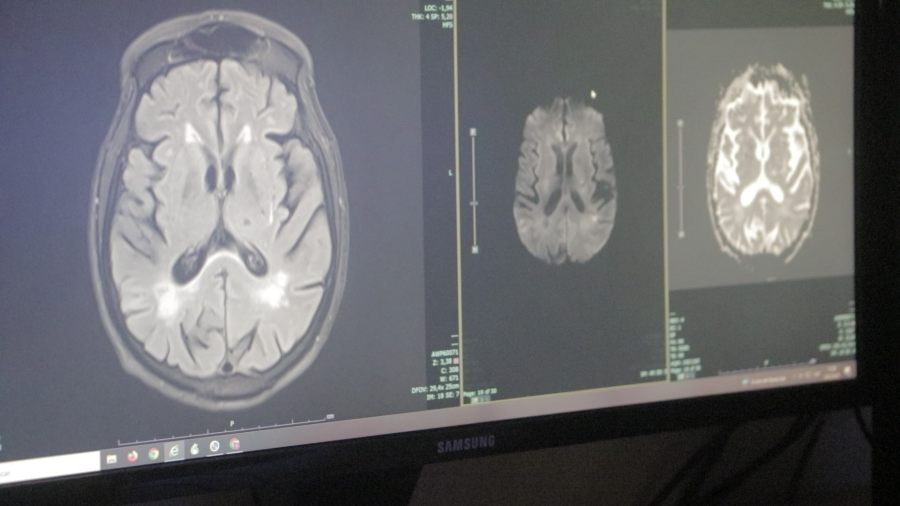

“·Son muy novedosas, no se hacen en todas las provincias y este hospital sí lo ha ofrecido: son las cirugías de epilepsia en sus diferentes formas, llamadas cirugías receptivas, de desconexión, y terapia de inmunomodulación”, destacó Hardaman.

El Madariaga ha tenido 14 pacientes que cumplían con los criterios de epilepsia muy severa, “que nosotros denominamos fármaco resistente. Y la verdad que la respuesta ha sido muy exitosa. Trabajamos en colaboración con el servicio de Neurocirugía y con profesionales que vienen de afuera a la hora de abordar esta patología”, destacó Hardaman